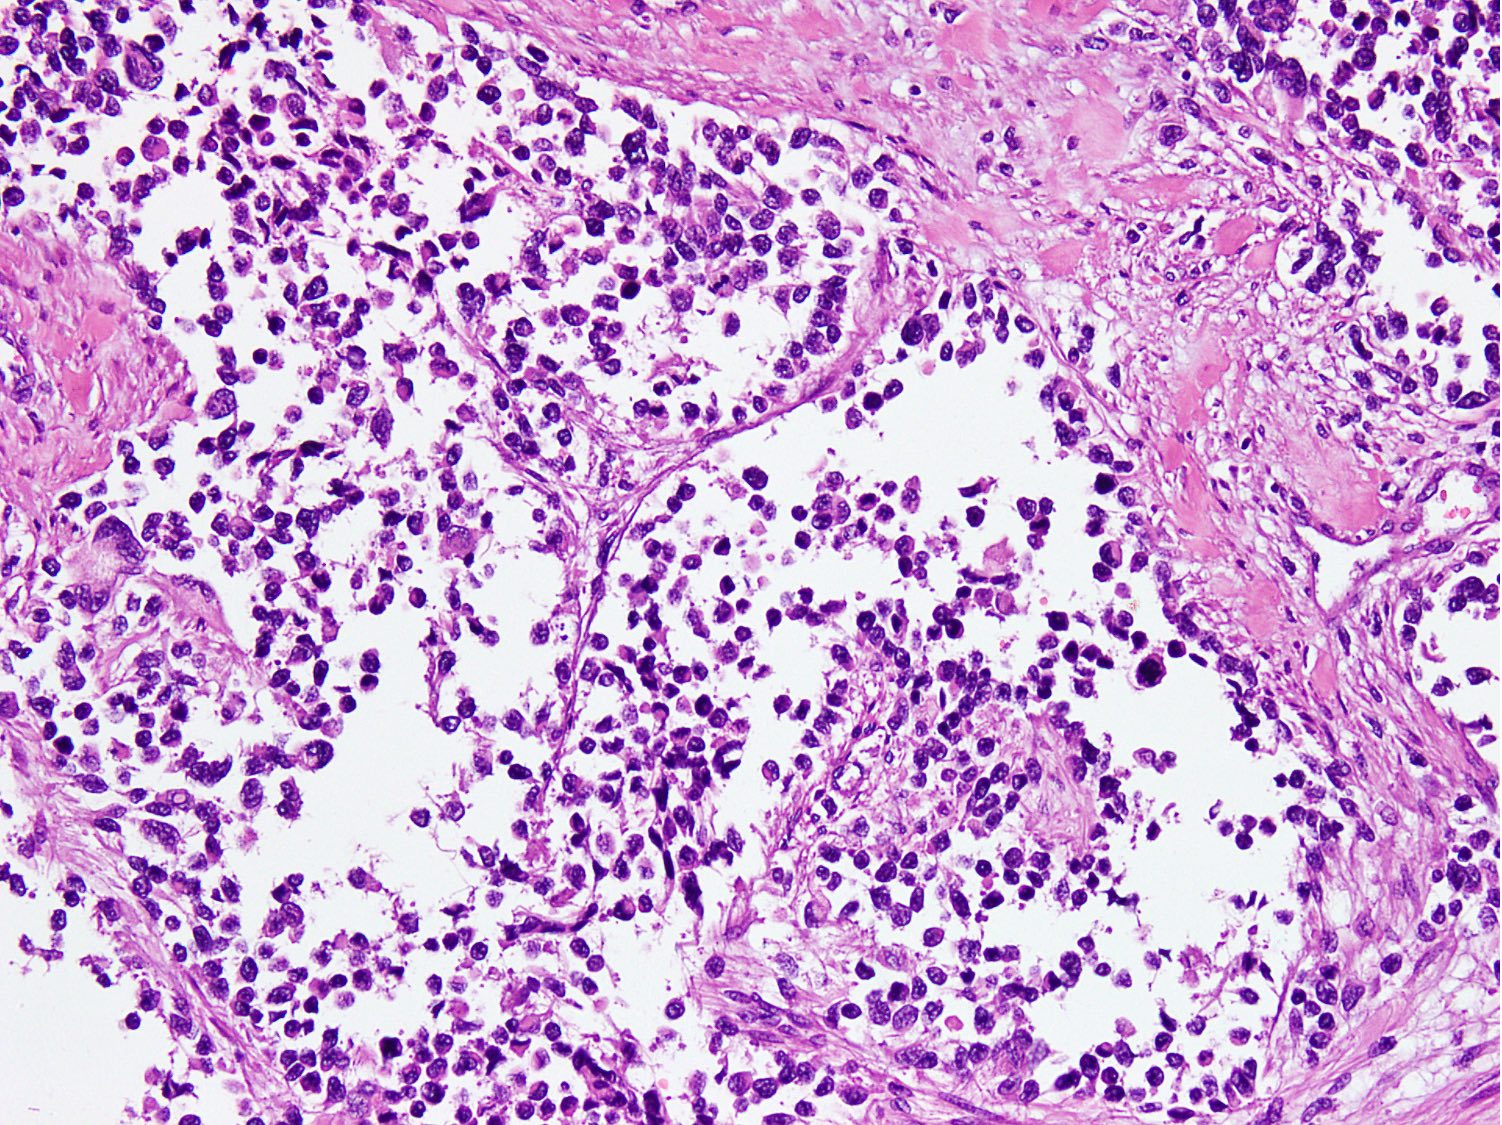

Microscopic (histologic) description

- Large clusters, nests, cords and trabeculae of primitive round cells, separated by variably thick fibrovascular septa

- Loss of cellular cohesion in the center forms alveolar-like, cystic and vague papillary appearance (Histopathology 2022;80:98)

- Layer of cells adheres to the periphery of the spaces and fibrous septa

- Cells in the center have poor preservation and are necrotic; may appear floating

- Multinucleated tumor giant cells with wreath-like lineup of nuclei are common (Acta Pathol Microbiol Immunol Scand A 1982;90:345)

- Round to oval rhabdomyoblasts with abundant acidophilic cytoplasm may be present

- Brisk mitosis and variable tumor necrosis

Microscopic (histologic) images

Contributed by Nasir Ud Din, M.B.B.S.